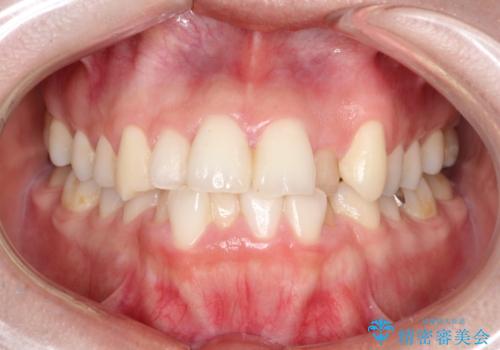

【ワイヤー矯正】前歯の凸凹を非抜歯で治療

- 前歯の凸凹を主訴に来院されました。

側方拡大にてスペースを作ることにより綺麗に前歯を並べることができました。

前歯の凸凹がある場合は治療計画を立てる上でスペースをどのように作るかが重要になります。

今回の場合は主に側方拡大でスペースの確保を行いました。